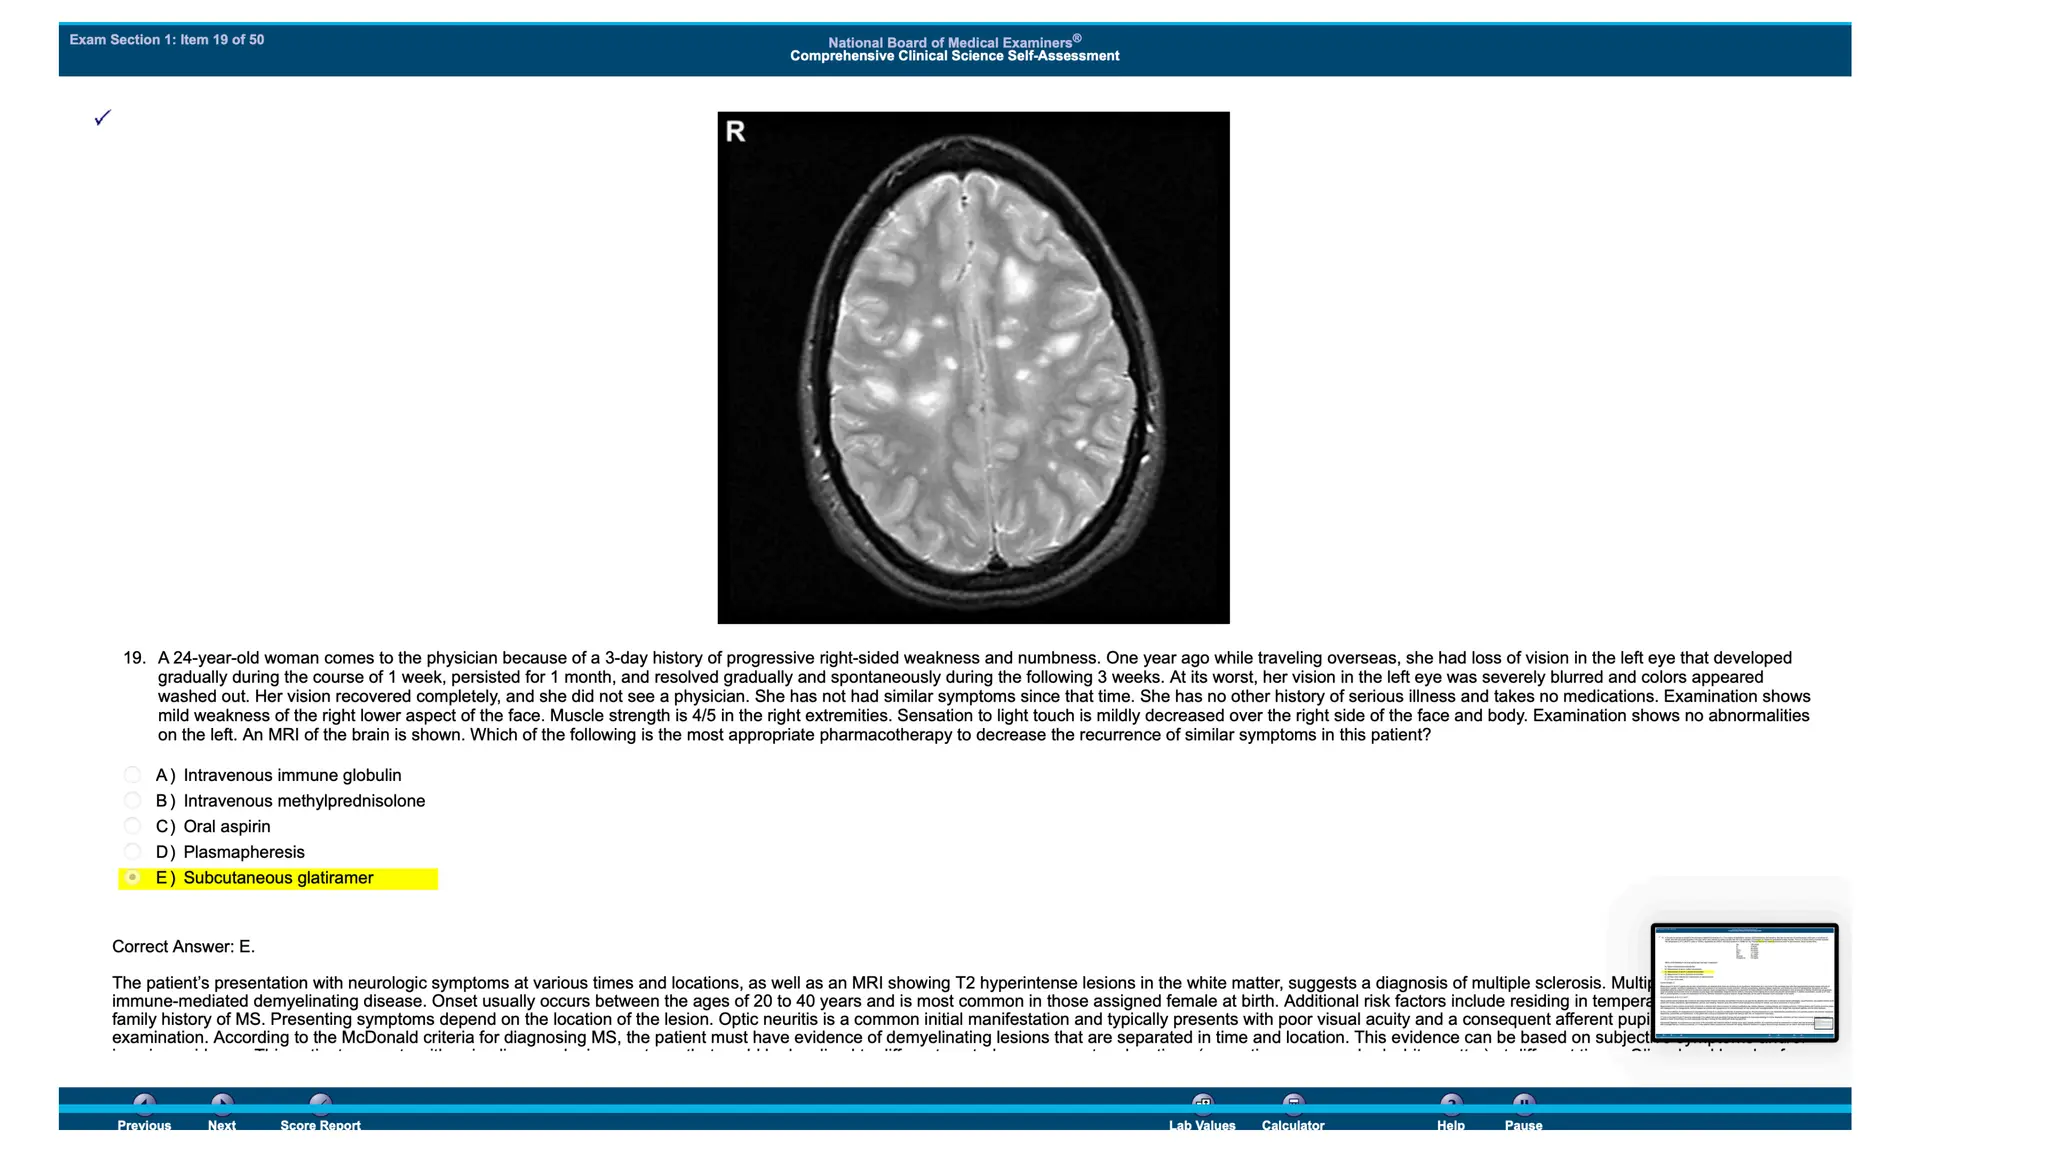

IgA Nephropathy: overview of Clinical trials (Journal Club) NBME 14 - ANSWERS.pdf for usmle step 2 CK